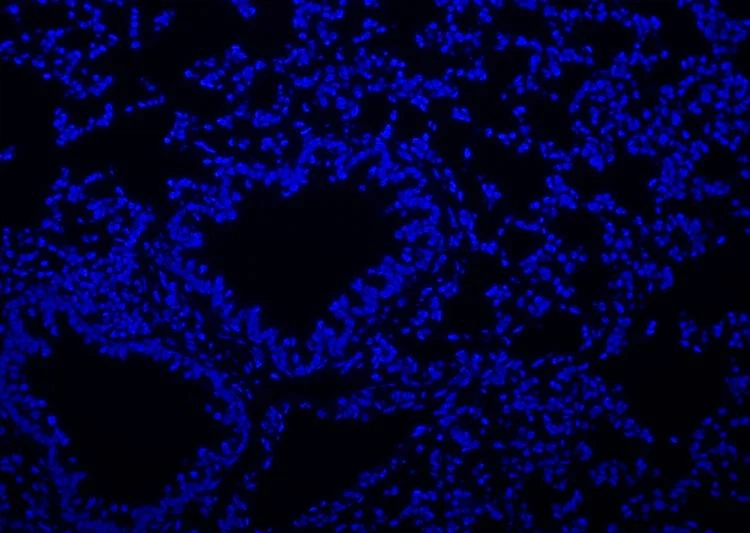

Hoechst 33258 का आणविक सूत्र C25H24N6O·3HCl है, आणविक भार 533.88 है, और CAS संख्या 23491-45-4 है। होचस्ट 33258 एक नीली फ्लोरोसेंट डाई है जो कोशिका झिल्ली में प्रवेश कर सकती है, और डबल-स्ट्रैंडेड डीएनए के साथ संयुक्त होने पर इसकी फ्लोरोसेंस काफी बढ़ जाती है। अधिकतम उत्तेजना तरंगदैर्ध्य 346 एनएम है, और अधिकतम उत्सर्जन तरंगदैर्घ्य 460 एनएम है। होचस्ट 33258 का उपयोग आमतौर पर एपोप्टोसिस का पता लगाने, परमाणु धुंधलापन, या नियमित डीएनए धुंधलापन के लिए किया जाता है। इसका उपयोग स्थिर कोशिकाओं और ऊतकों या गैर-स्थिर कोशिकाओं और ऊतकों के नाभिक को दागने के लिए किया जा सकता है। धुंधला होने के बाद, इसे प्रतिदीप्ति माइक्रोस्कोप द्वारा देखा जा सकता है या फ्लो साइटोमेट्री द्वारा पता लगाया जा सकता है। जब प्रतिदीप्ति सूक्ष्मदर्शी द्वारा देखा जाता है, तो यह पराबैंगनी प्रकाश, जो नीली प्रतिदीप्ति है, से उत्तेजित होता है।

यह उत्पाद उपयोग के लिए तैयार समाधान है, जिसकी सांद्रता सभी प्रकार की नियमित धुंधलापन की जरूरतों को पूरा करने के लिए अनुकूलित है।